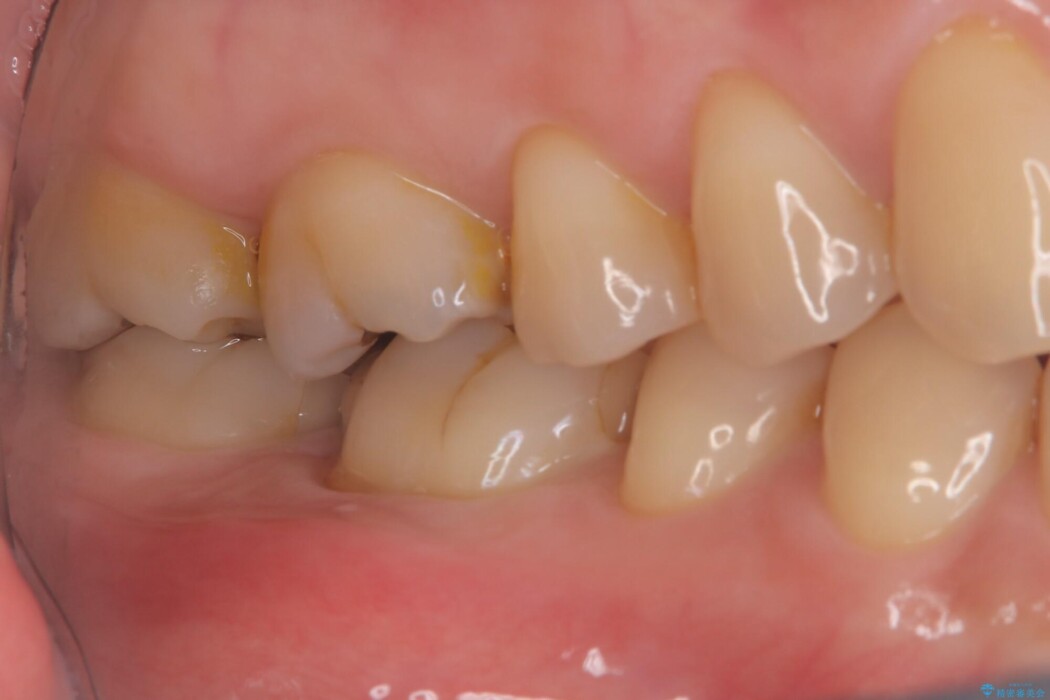

術後の経過は非常に良く、あんなに大きかった膿の袋は消え、健康な骨が再生しているのが確認できました。痛みや腫れも消えて抜歯を免れ、現在は被せ物を入れてしっかりお食事を楽しんでいただけるようになっています。